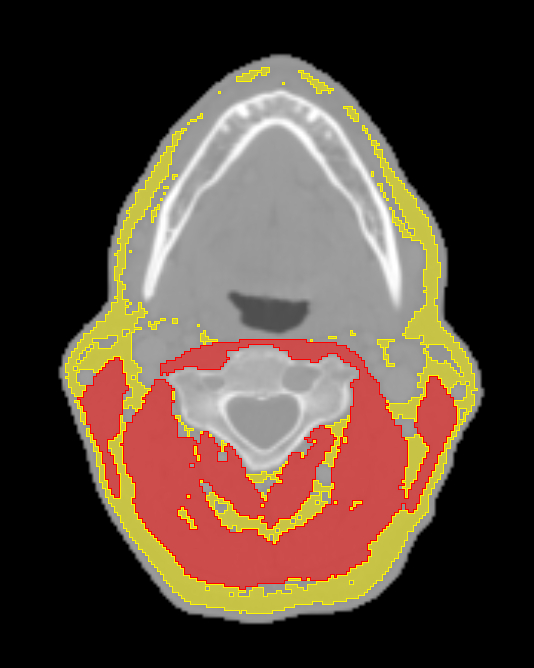

Methods Patients with HNC treated with RT at a tertiary center between 2005 and 2010 were identified. Oncologic CT scans of the neck performed for RT planning purposes were used to quantify adipose tissue and skeletal muscle mass at the C3 spinal level by SliceOmatic, version 5.0 Tomovision (Figure 1). Adipose tissue and skeletal muscle volumes were indexed to account for height. Fine-Gray competing risk regression models with stepwise forward selection were used to evaluate the association between baseline clinical and imaging characteristics with subsequent development of the composite event of new or worsened carotid atherosclerosis, carotid artery stenosis >50%, transient ischemic attack (TIA) or stroke.